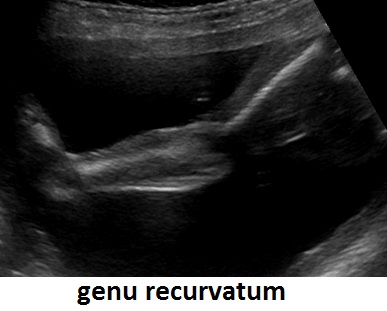

Quella che interessa dal punto di vista della diagnosi ecografica prenatale è l'Osteogenesi Imperfetta tipo II (OMIM 166210) caratterizzata da fragilità ossea con fratture multiple, micromelia severa dovuta alle fratture delle ossa lunghe, ipoplasia toracica severa a volte con fratture costali, ipomineralizzazione diffusa del cranio.  Ecograficamente si manifesta con ossa corte, ricurve e fratturate (le ossa fratturate si presentano angolate); ossa craniche scarsamente ossificate (tanto che la volta cranica può avere una ecogenicità simile a quella della linea mediana) con conseguente migliore evidenza e definizione delle strutture cerebrali e segno caratteristico la deformabilità della teca cranica.;  ipoplasia toracica con fratture costali; IUGR; movimenti fetali scarsi.